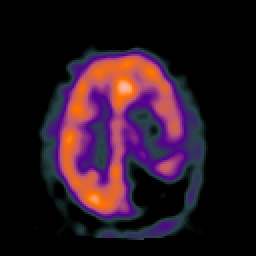

SPECT TC Study #2 -- Slice #36

[Home][Help][Clinical][Tour 1][Tour 2][Tour 3] Slice 36